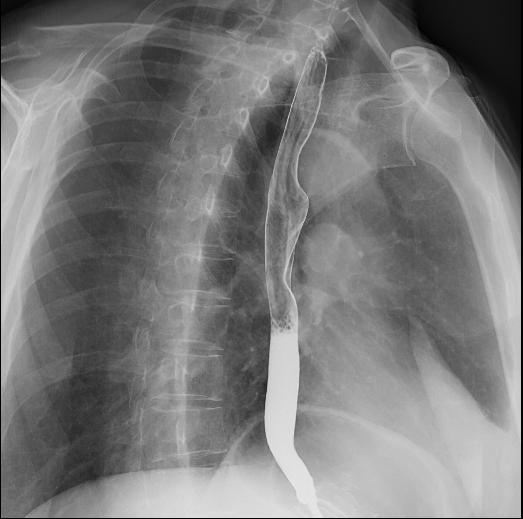

食道造影

食道长轴、胃全景、胃小沟与胃小区局部放大精细数字图像、下消化道全景等;